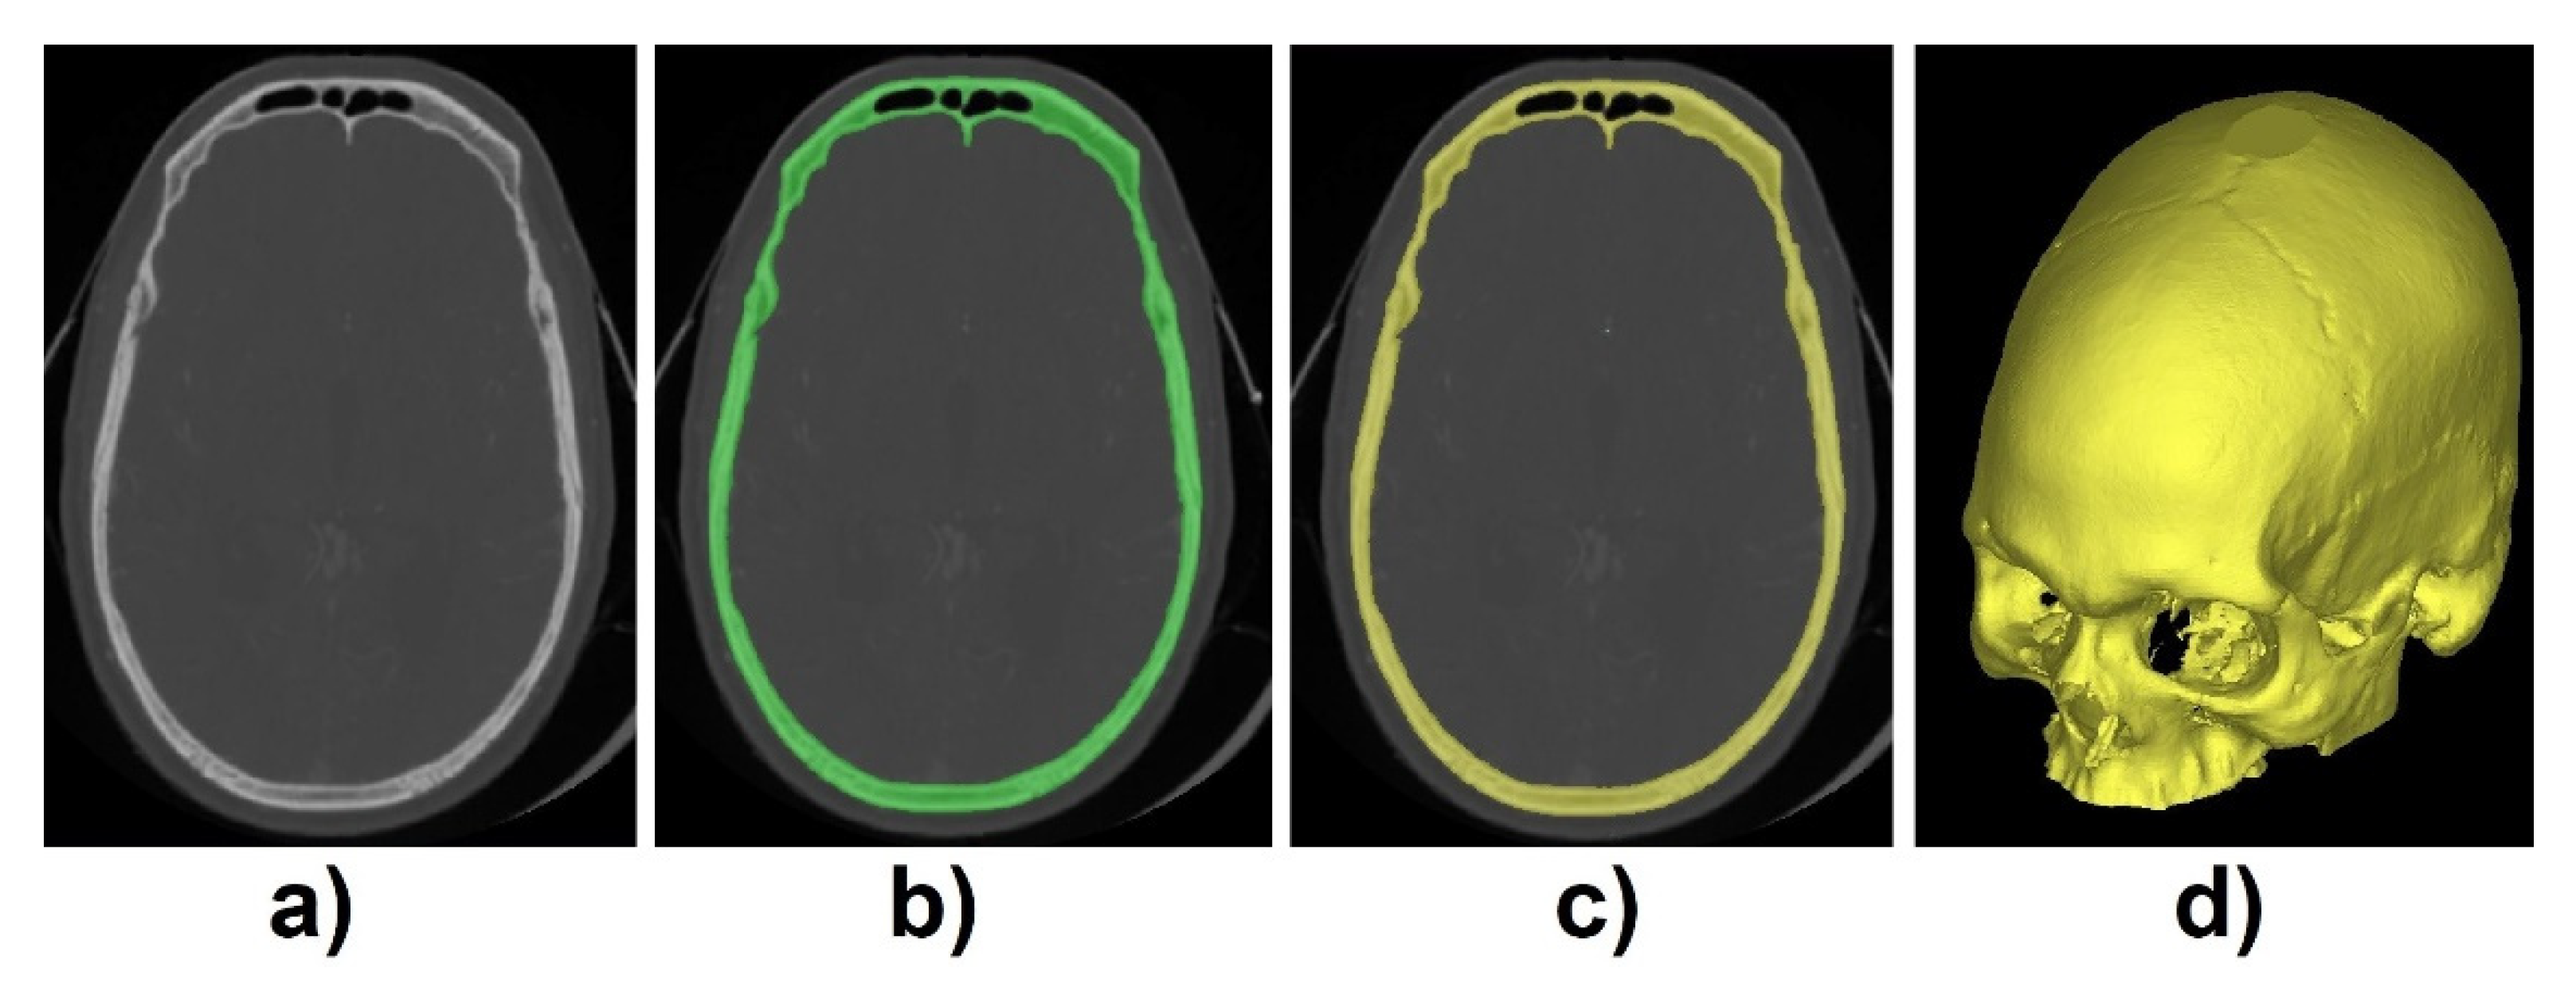

2.1. Data Processing

3.1. Skull Segmentation